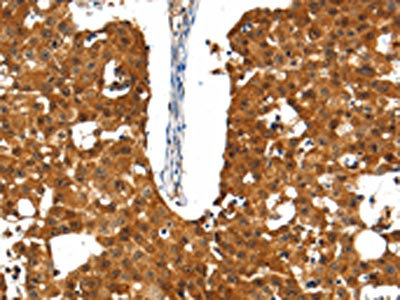

The image on the left is immunohistochemistry of paraffin-embedded Human breast cancer tissue using CSB-PA254587(SSTR5 Antibody) at dilution 1/30, on the right is treated with synthetic peptide. (Original magnification: ×200)